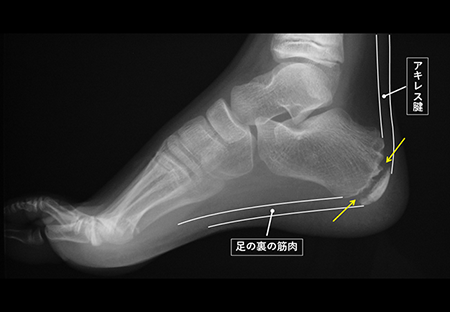

発育期の子どもの骨は、大人と違い、骨が成長していく部分(骨端線あるいは成長軟骨と言います)が残っています。(下図の矢印)

骨端線は物理的に弱く、かかと部分の骨(踵骨)には、アキレス腱と足の裏の筋肉がついているため、運動で繰り返し骨端線の周囲にひっぱる力が加わることで、炎症を起こしたり、骨に細かい傷がついたりすることが痛みの原因と言われています。